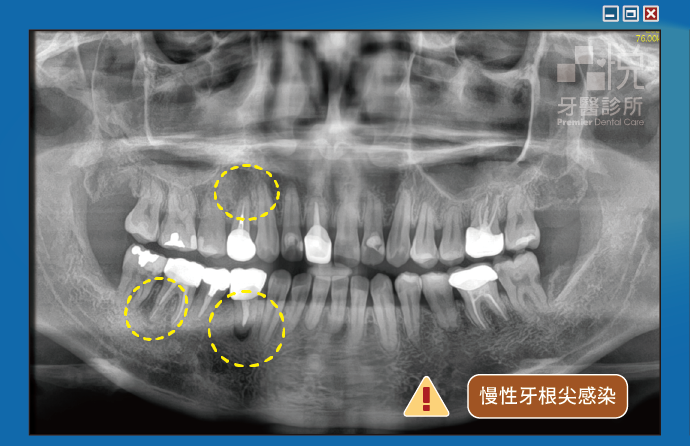

如果根管治療時因為根管鈣化而無法順利消毒並封頂,也可能造成慢性牙根尖感染引起膿包。